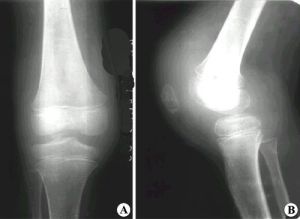

多數膝關節滑膜炎,是在上述各種膝關節損傷等情況下並發的,但也可以單獨發病或繼發於膝關節骨關節炎,後者多為老年人。在青壯年人多有急性膝關節外傷史,傷後膝關節開始發生輕度水腫、疼痛、活動受限及跛行。通常在傷後6---8小時出現滑膜反應性積液,膝關節明顯腫脹、發熱,不敢活動。檢查發現膝關節屈伸活動受限,下蹲困難並伴有疼痛,關節周圍可有局限性壓疼點,浮髕試驗陽性。慢性損傷性滑膜,可能無明顯外傷史,主要表現膝關節發軟及活動受限,腫脹持續不退,不敢下蹲。活動增多時加重,休息後減輕。久病者,可捫到膝關節囊肥厚感。對膝關節積液多者或反覆出現積液者,可做關節積液檢查,它能反應出滑膜炎的性質及其嚴重性。故關節穿刺和滑液檢查,對膝關節滑膜炎的診斷和鑑別診斷,均有重要參考價值。